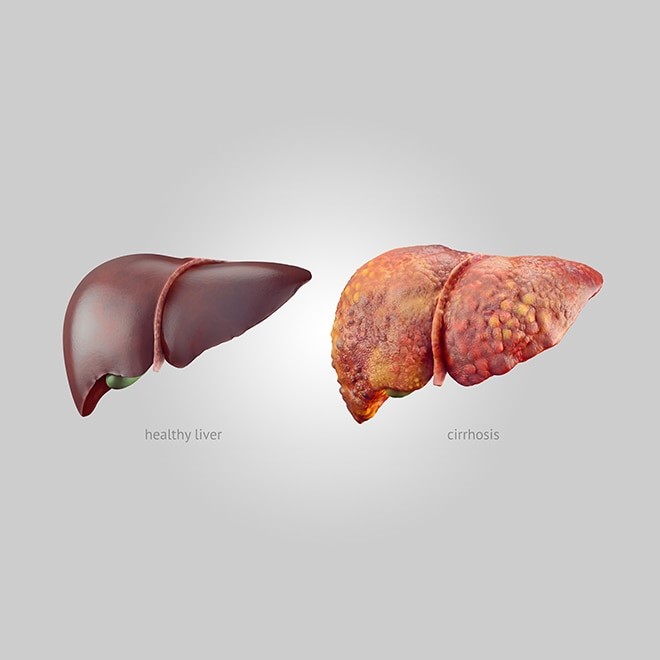

متاستاز کبدی چیست؟ متاستاز کبدی به گسترش تومور سرطانی که در بخش دیگری از بدن شروع شده است به کبد، گفته میشود. به متاستاز کبدی، سرطان کبد ثانویه هم میگویند. سرطان کبد اولیه سرطانی است که منشا آن کبد است و بیشتر در کسانی دیده میشود که عوامل زمینه سازی مانند هپاتیت یا سیروز کبدی دارند.

متاستاز کبدی چیست؟ متاستاز کبدی به مرحله ای از سرطان بخشهای دیگر بدن گفته میشود که به کبد سرایت کرده (متاستاز داده) است. در این مرحله درمان بسیار مشکل است. اما با انتخاب رویکرد مناسب، میتوان رهایی از بیماری و حتی درمان قطعی را برای برخی بیماران میسر ساخت.